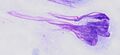

-

Smearing of cells across a glass plate may cause smearing artifacts, such as the nuclear smearing of this monocyte, shown as tail-like extension of nuclear material.